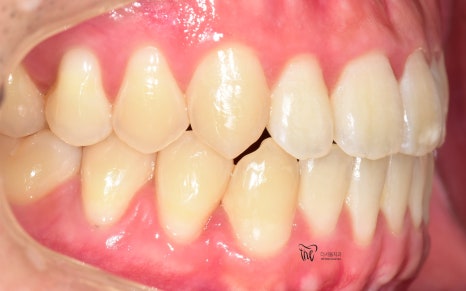

정면 및 측면에서 봤을 때, 측절치의 후방위치에

따라서 반대교합 형태를 보여주고 있으면서

이 때문에 송곳니가 더 덧니처럼 보여지는 느낌을

받고 있는 모습을 볼 수 있습니다.

치열이 많이 가지런하게 펴진 것을 볼 수 있고,

그간 치과에 자주 오셨기 때문에 교정유지기 를